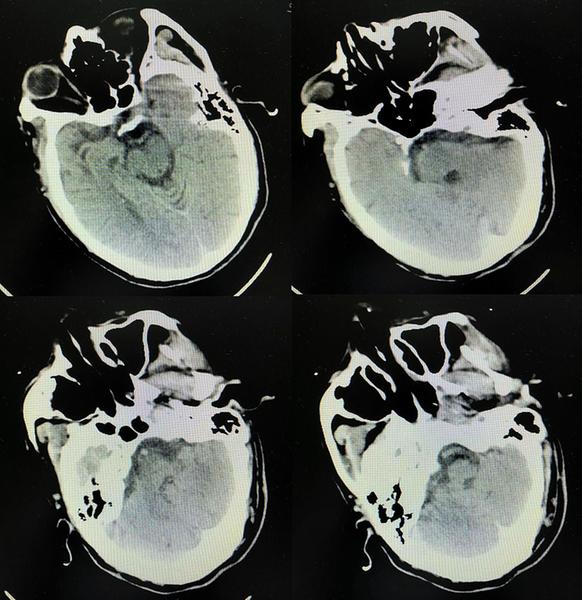

颅脑CT未见出血

颅脑DWI示左侧小脑半球、左侧颞叶、双侧枕叶急性脑梗死